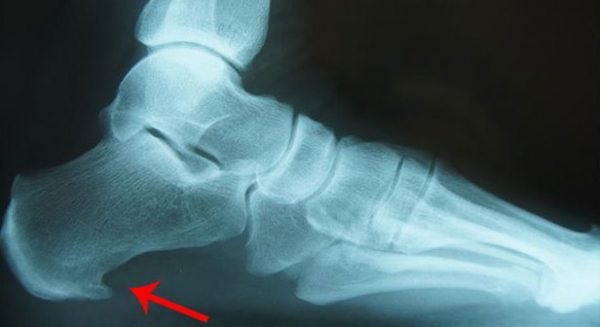

El diagnóstico es clínico, teniendo estos datos ya lo tenemos. A priori, no necesitamos nada más. Pero si queremos hacer alguna prueba de imagen, nos bastará normalmente con una radiografía simple. Aquí podremos ver, habitualmente, el famoso espolón calcáneo

Y en este punto nos encontramos ante lo más difícil de esta patología... Explicar al paciente de que lo que le duele es la fascia, no el espolón. Que el espolón no duele, que es consecuencia de la fascitis (por el proceso inflamatorio, la inserción de la fascia se calcifica).

Y esto también es algo que médicos de cabecera tiene que tener claro para no dar información errónea al paciente. El espolón no duele, y el espolón no se opera. En breve veremos qué se opera...